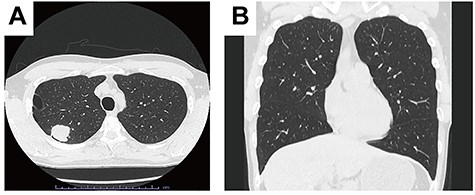

Intravenous indocyanine green delineation of the interlobar border between the right upper and middle lobe.

Indocyanine green was intravenously injected after transection of the pulmonary artery, vein and bronchus by robotic staplers. The interlobar fissure was identified by near-infrared fluorescence imaging camera and divided by robotic staplers.